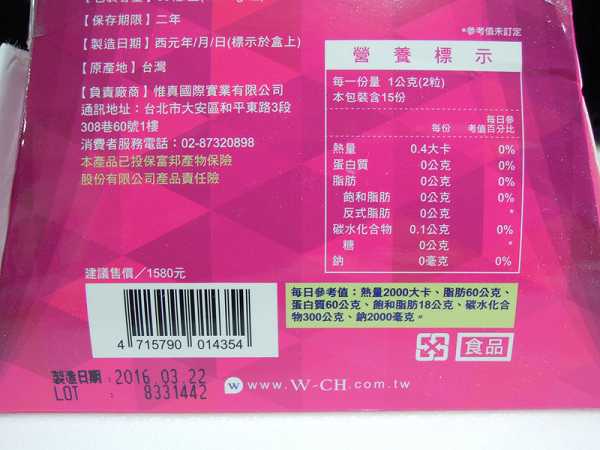

每一盒Supercut塑魔纖立塑膠囊都有三小包,每一小包有10顆膠囊

Supercut塑魔纖立塑膠囊的成分有:瓜拿那萃取粉、肉桂萃取粉、辣椒萃取物(唐辛子)、吡啶甲酸鉻、番瀉葉粉末、玉米澱粉、氧化鎂、二氧化矽。

食用方式:早晚餐前30分鐘各1粒,每日不超過2粒。(多食無益)

包裝是桃紅色的

番瀉葉萃取物每日食用限量為12mg以下,